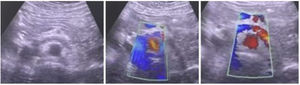

Preoperative assessment – inclusion criteriaAll the patients that had congestive pelvic syndrome confirmed with abdominal veins Doppler ultrasound or angioCT, were taken to diagnostic and/or therapeutic cavography and to pelvic veins phlebography. During the cavography and pelvic veins phlebography the patients could present centripetal vein flow, varicose pelvic veins, and signs of NCS with lumbar veins flow derivation, severe incompetency, and dilatation of left gonadal vein, circumaortic veins, stenosis of the LRV-caval union and fumarole LRV sign. If the patient presented any of the previously mentioned signs, then was taken to LRV – inferior vena cava (IVC) pressure measurement comparison using a multi-purpose terminal unique orifice catheter with an arterial line transductor in the venous central pressure modality (the LRV–IVC pressure measurement comparison was positive for NCS if the difference of pressure was equal or higher to 3mmHg).

Surgical techniqueThe principles applied were urgent LRV pressure control, treatment of the hematuria, venous drainage derivation and congestive pelvic syndrome origin resolution. All the patients remain 24h postoperative in hospital observation. The repair was performed via endovascular access, after local anesthesia and sedation. The right common femoral and the left internal jugular vein was punctured with ultrasound guide and a 6F introducers sheath were inserted. The LRV was catheterized with a Cobra 2 5F diagnostic catheter and phlebography was performed. This confirmed critical stenosis of the LRV and the pelvic varicose veins on the left, with a dilated left gonadal vein (Fig. 1). The stenosis pressure gradient was measured in all patients. Through the internal jugular access, balloon LRV angioplasty was performed (Fig. 2) and then deployment of a e-Luminex self-expanding nitinol bare metal arterial stent (10–12mm×40mm) (Figs. 3 and 4) was performed resolving the NCS (Fig. 5). Additionally, identified pelvic varicose veins were embolized using Concerto coils (20mm×50mm) through the basilic vein using a multi-purpose catheter. No dietary restrictions were imposed, and oral food intake was initiated in the first 3 postoperative hours. No need for a postoperative ICU. Postoperative anticoagulation for 6 months using rivaroxaban and then switching to salicylic acid for another 6 months was prescribed to all patients. The postoperative patients follow-up was performed using Doppler ultrasound in the 6 months and physical examination in all face-to-face clinical outpatient consults.